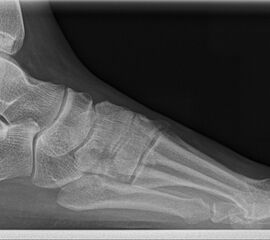

Abbildung 1: Plantarer und dorsaler Sporn im Röntgenbild und im MRT

Abb. 1a und Abb. 1b: großer dorsaler Fersensporn und ein minimaler plantarer Sporn, Patient, 50 Jahre.

Dorsaler Fersensporn: Dorsale Fersenschmerzen können auch durch einen echten dorsalen Fersensporn entstehen (siehe Abb. 1). Dieser entsteht als knöcherne Ausziehung durch Verkalkung der Achillessehne an ihrem Ansatz.